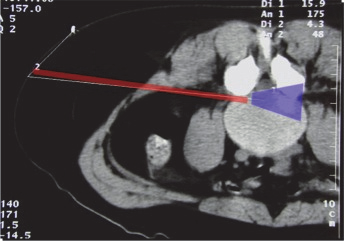

It is the “Kambin triangle” (the safe corridor to the lumbar disc between the exiting nerve root and the superior facet) which reminds us of his pioneering work (Figure 9).

圖片關鍵詞

Figure 9: Kambin’s triangle for a safe posterolateral approach.